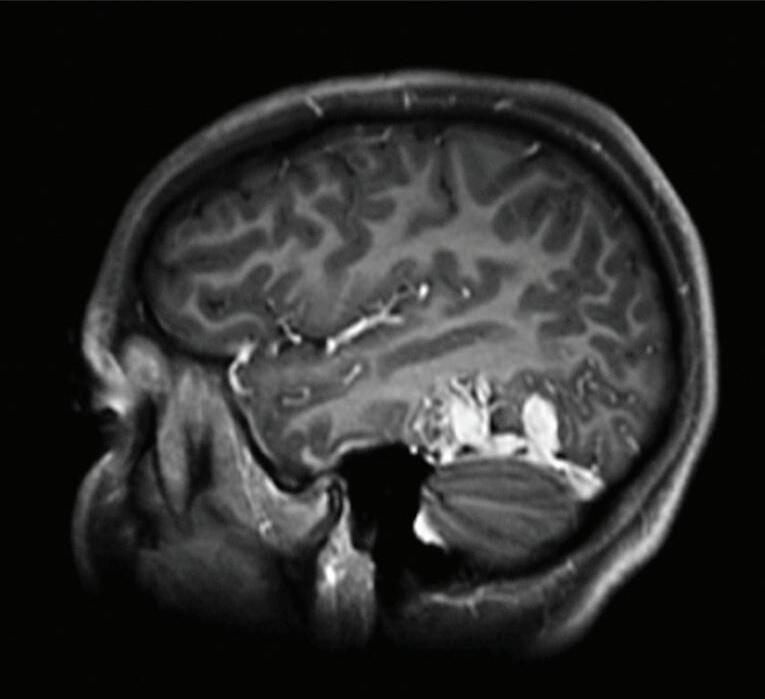

Fig. 1-20. RNM T1 com contraste em cortes (a) axial e (b) sagital e (c) FLAIR axial, demonstrando MAV do giro fusiforme esquerdo com presença do aneurisma pós-nidal (setas azuis). Angiografia pré-operatória em (d) AP e (e) em perfil mostrando a MAV anteriormente descrita, nutrida por ramos da artéria cerebral média e posterior esquerda, com drenagem superficial para o seio transverso e sigmoide ipsilateral e aneurisma pós-nidal venoso (setas azuis). (f) Visão intraoperatória do aneurisma pós-nidal (seta azul).